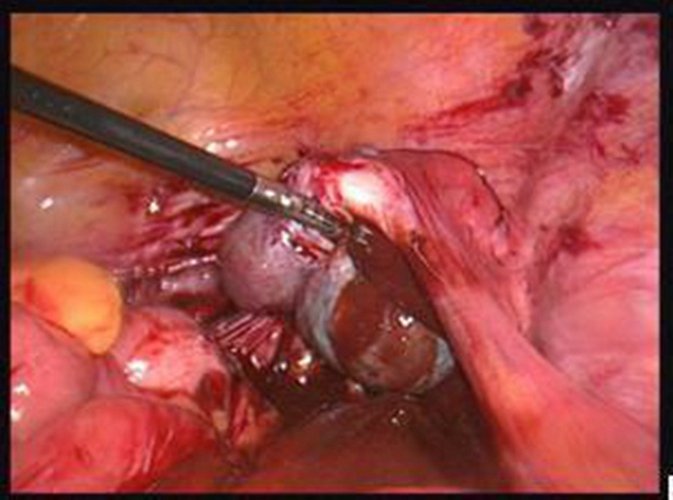

巧克力囊腫圖片

輸卵管囊腫手術

手術後巧克力囊腫

實拍巧克力囊腫